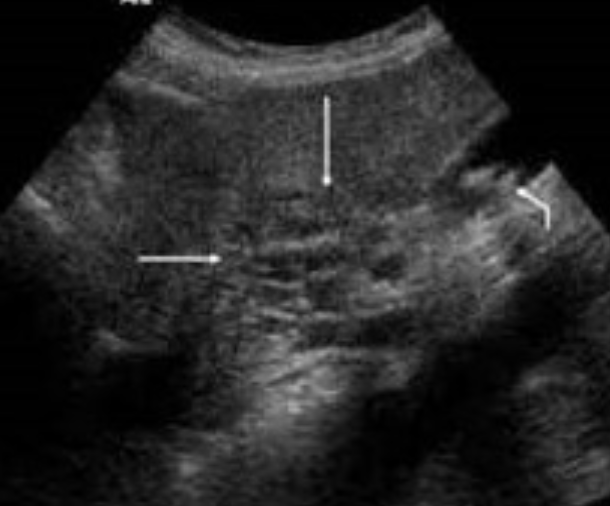

2D US: pancreas enlargement, hypoechoic parenchyma from edema, irregular ill-defined borders, peripancreatic free fluid, peripancreatic echogenic inflammatory fat, can have focal areas of inflammation/hypoechoic tissue

Acute Pancreatitis → sudden inflammation of pancreas from blockage of ducts and increased secretions

clinical hx: gallstones in bile duct, alcohol abuse, obstruction/mass, endoscopy, trauma, drugs, transplant

s/sx: increased amylase (not as useful), increased lipase (more specific), sudden severe epigastric pain, pain radiating to mid back, LUQ pain, N&V, fever, increased WBCs, jaundice (if biliary obstruction)